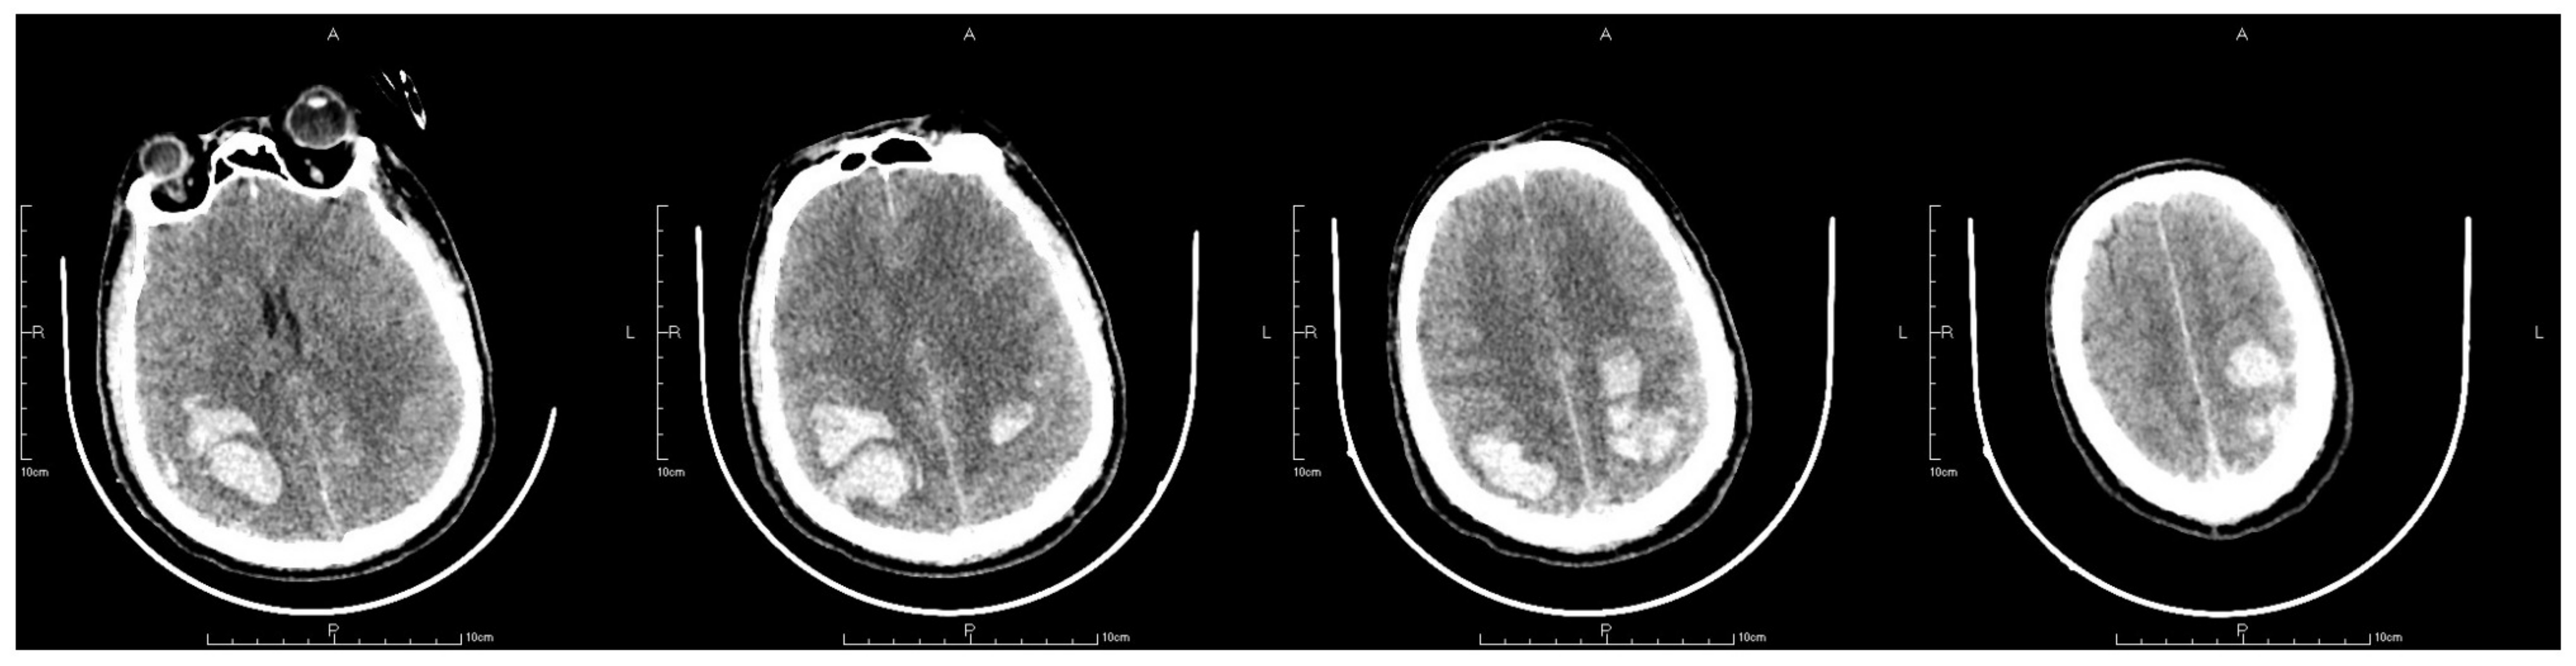

2. Case Presentation

2.4. Postoperative Management